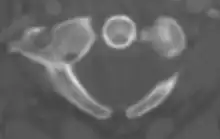

An axial CT scan showing a posterior arch defect

Foramen arcuale or a bony bridge above the vertebral artery on the posterior arch of the atlas may be present. This foramen has an overall prevalence of 9.1%.[8] Arch defects refer to the condition where a gap or cleft exists at the anterior arch or posterior arch of the atlas. The prevalence of the posterior arch defect and anterior arch defect was 0.95% and 0.087%, respectively.[9] The anterior arch defect may be presented along with posterior arch defect, a condition known as combined arch defect or bipartite atlas.[10]